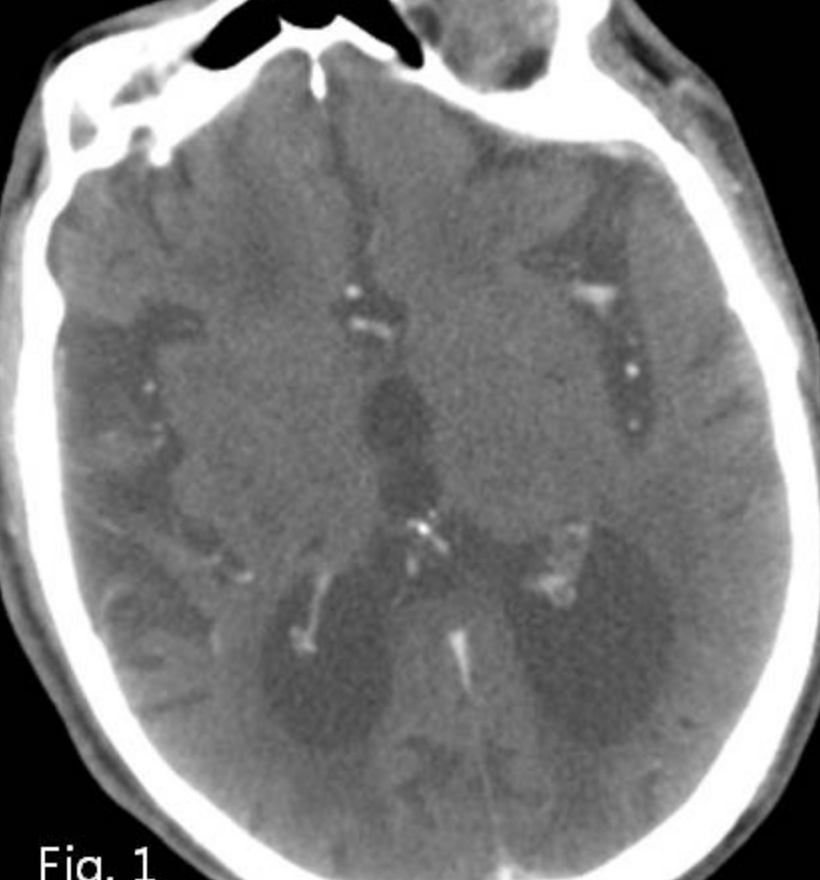

Fig. 1

Contrast enhanced CT scan shows diffuse brain atrophy due to hypoxic brain damage.